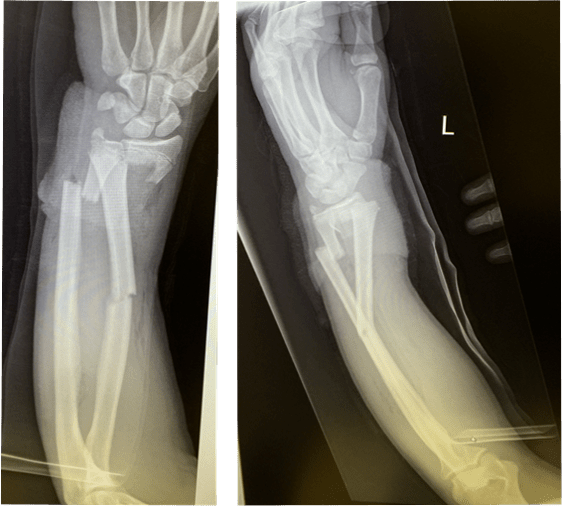

请大夫们帮忙看看十岁小孩右前臂桡尺骨双骨折的片子

11岁男孩前臂骨折